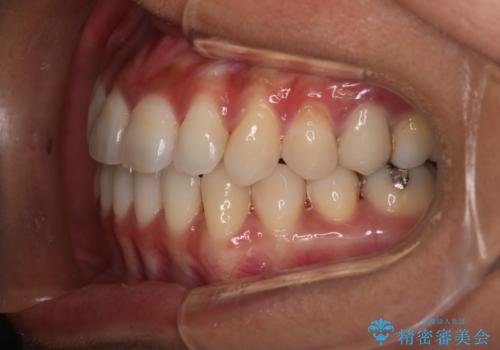

- 開咬を主訴に来院されました。前歯部に開咬、右側大臼歯部にクロスバイトが認められます。ワイヤー矯正の審美装置で治療し、ゴム掛けを行いながら噛み合わせを改善しました。

主訴である開咬と右側大臼歯部クロスバイトを改善でき、しっかりと噛むことができるようになりました。